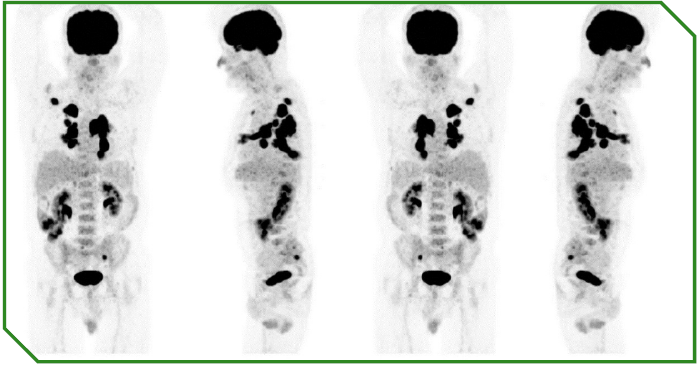

Paciente masculino de 65 anos, previamente sem comorbidades, diagnosticado com carcinoma espinocelular de língua, tratado inicialmente com cirurgia e radioterapia adjuvante, evoluindo precocemente com doença metastática pulmonar e óssea. No momento da avaliação oncológica, apresentava performance status comprometido e alta expressão de PD‑L1 (CPS 30). Optou-se por imunoterapia isolada em primeira linha, considerando perfil clínico e objetivo de redução de toxicidade, com acompanhamento longitudinal e intervenções locais conforme necessidade.